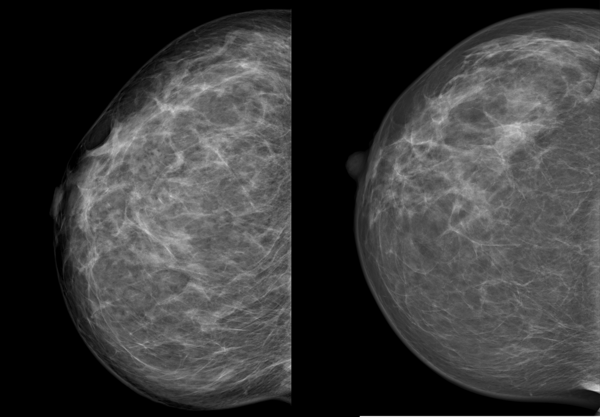

Von jeder Brust werden üblicherweise zwei Aufnahmen - jeweils von oben nach unten (cranio-caudale Aufnahme) und schräg von innen nach außen (medio-laterale oblique Aufnahme) - angefertigt. Die Brust wird dabei in eine Vorrichtung eingespannt und komprimiert:

Die cc-Aufnahme wird immer so dargestellt, dass die Außenseite der Brust im Bild oben liegt.

können die Brustabschnitte in der Nähe der Achsel besser dargestellt werden.

Die Kompression beeinflusst die Qualität der Aufnahme. Je dünner die Brust ausgestrichen ist, desto besser und klarer wird das Bild, wie das Beispiel unten zeigt.

Wir sehen dieselbe Brust im Abstand von zwei Jahren, die linke Aufnahme ist die neuere. Links erscheint die Brust wesentlich dichter, das Drüsen- und Bindegewebe ist unscharf, die Haut um die Brustwarze ist nur unzureichend abgebildet. Verdächtige Veränderungen könnten eventuell durch die schlechte Bildqualität überdeckt werden. Die Frau hatte an diesem Tag eine sehr druckempfindliche Brust, weshalb keine stärkere Kompression möglich war.

Eine gute Kompression ist für die Qualität der Aufnahme leider unumgänglich. Wir bemühen uns deshalb, möglichst behutsam und schonend vorzugehen.